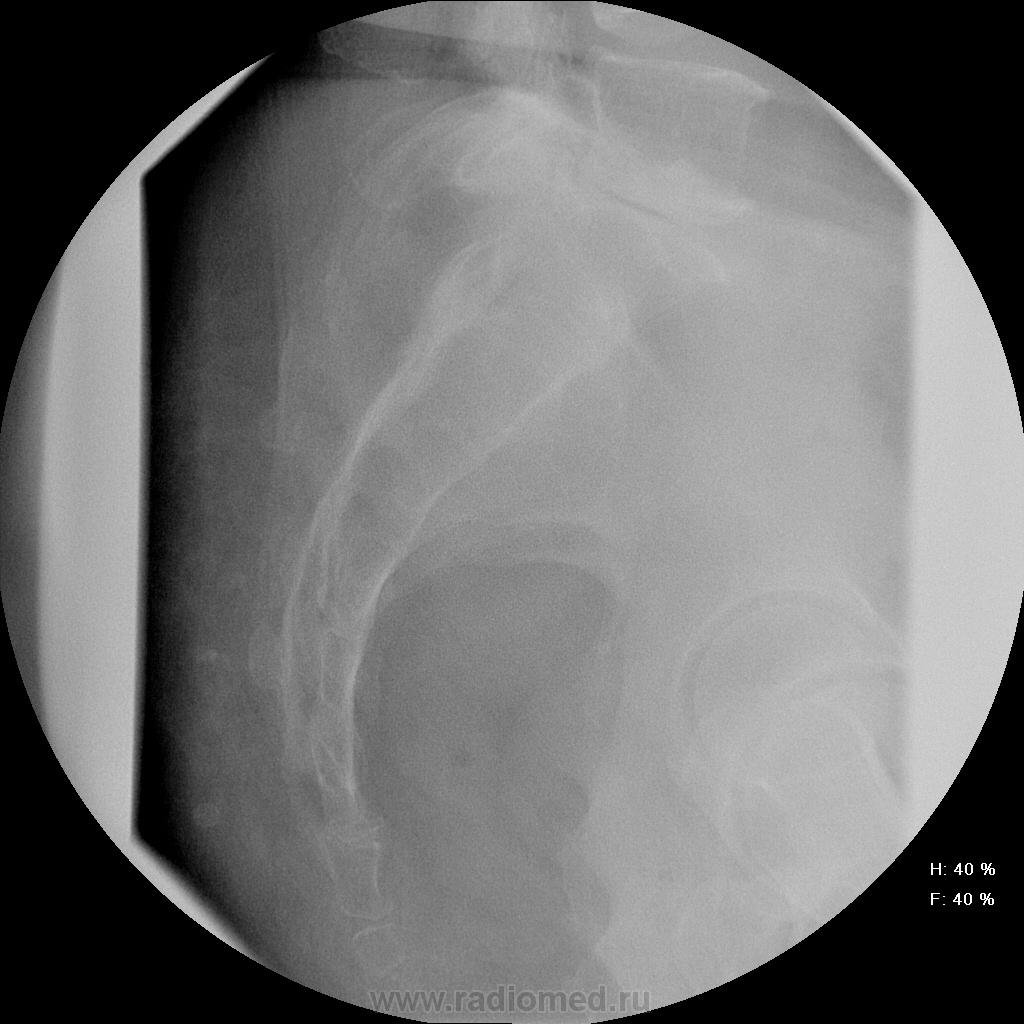

Женщина 55 лет, полная, поступила в неврологическое отделение с жалобами на боли в т.бедренных суставах,  области паха, больше слева. Лечили в поликлинике ДОА, остеохондроз- без эффекта, и направлили в стационар.

Остеохондроз от нижнегрудных позвоночно-двигательных сегментов и ниже, резко выраженный на уровне L5-S1 (3 степень снижения диска). Неполная люмбализация S1 - видны псевдосуставные щели на уровне боковых масс. Аномалия тропизма L5-S1: разноплоскостная ориентация щелей межпозвоночных суставов, один ближе к горизонтальной, второй - ближе к кософронтальной. Гиполордоз. Сколиоз. Деформирующий спондилез. Коксартроз 1 ст. с оссификацией крыш впадин. Флеболит(?!) в малом тазу слева, исключить конкремент в тазавой части левого мочеточника (ОАМ и т.д.; главное - экскреторная урография, желательно с прицельной РГ области мочевого пузыря в левой косой проекции на минуте 15-25).

а что это за тень по задней поверхности н/3 крестца в боковой проекции?

Тень, весьма похожая на конкремент.

Ну раз мнений больше нет - Мы заподозрили деструкцию в области тела подвздошной кости над вертлужной впадиной слева и отправили на КТ (обратите внимание на разряжение костной структуры по сравнению с правой стороной). На КТ : множественные очаги деструкции позвонков , больше пострадал остистый отросток L4. Такие же очаги в тазовых костях, наиболее крупный как раз слева над вертлужной впадиной. Левая половина крестца почти полностью разрушена. Кроме этого, очаги в печени, надпочечниках. Тело матки увеличено, в области придатков слева - кистозное образование. После этого посмотрели на наши сникми - почти сразу все увидели, особенно пропажу остистого отростка L4.

Имеем мтс, нужно теперь найти первичный очаг...